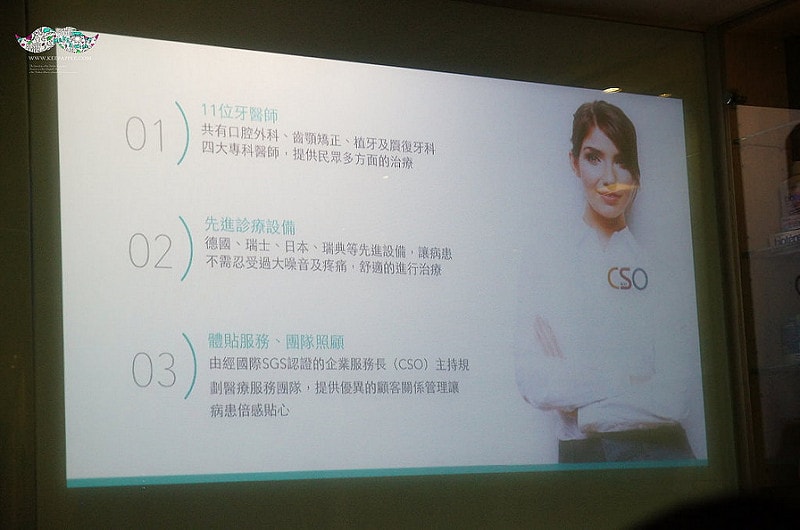

共有11位醫師輪流看診

悅庭牙醫診所的3D導航植牙系統也是一大特色

主要就是運用這台GPS導航植牙( i – Max 寰視導引植牙系統)的機器

多虧台大醫工所的研發製造

讓醫生可以更精準的處理病患植牙的正確位置

口腔狀況與細節都可以輕鬆掌握

將手術傷口面積可以降到最小的範圍

這套系統最重要的目的就是讓牙醫師在術前先進行過一次模擬植牙手術

利用電腦3D定位精準演算分析出植牙位置與角度

看要從哪個角度、深度進行植牙~

在經過預先演練以後牙醫師在真正動手術時,

既能節省時間又能大幅增加植牙成功率

加上悅庭牙醫的植體是使用來自瑞典的諾保科

是穩定且安全的全球植牙系統。